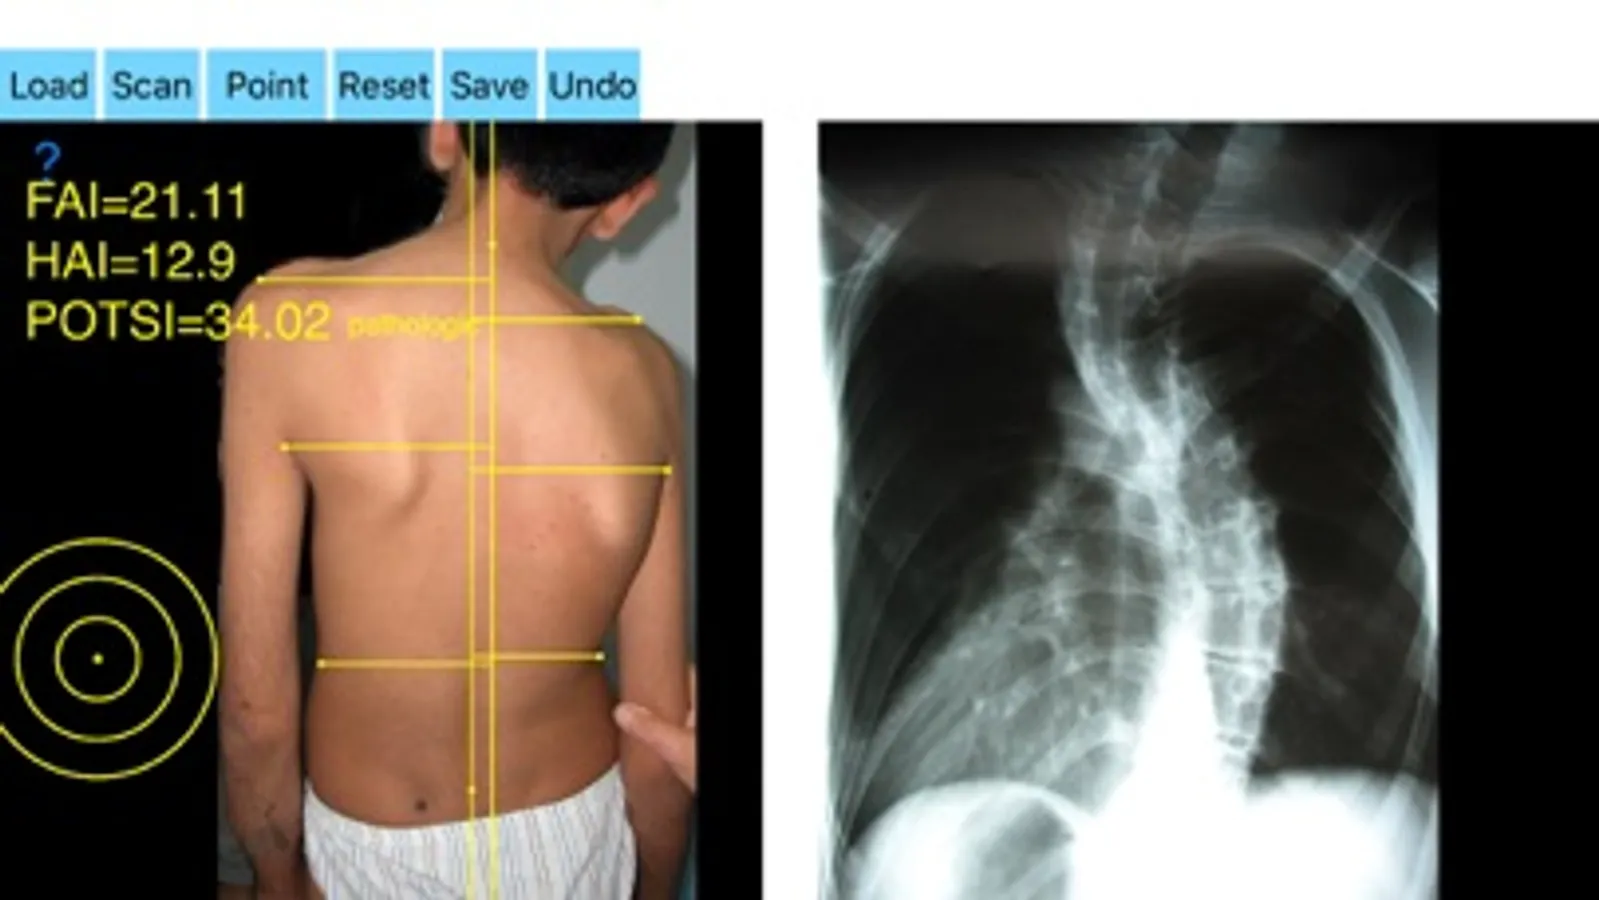

By visual inspection of the spine, asymmetry of the back is significant enough to suspect the existence of scoliosis in such cases, to evaluate spinal deformity an X-ray is ordered. Scoliometers could help evaluate the appearance of an asymmetric spine deformity with variable sensitivity and specificity but cannot substitute radiography. It is widely reported in the literature that significant correlations between radiographs and topographic parameters were found. Posterior Trunk Symmetry Index (POTSI) is a useful Index in the assessment of spinal deformity. POTSI Index is very sensitive in revealing any frontal plane asymmetry and could help identify moderate deformities which might otherwise be missed in clinics or physical examination. The Potsi Index is the sum two variables Height Asymmetry Index (HAI) and Frontal Asymmetry Index (FAI). Height asymmetry indexes are obtained as the sum of height differences of the shoulders, axillary folds, and waist creases, and it is normalized with the division of its value by the vertical distance from the C7 vertebra to the baseline of the gluteal cleft. The Potsi App calculates the Potsi Index according to the above mentioned developed topographic method (Suzuki N, Inami ) and offers a way to evaluate external back deformities with noninvasive technique. It is inexpensive and can be repeated indefinite times thus reducing unnecessary x-rays for normal anatomies and mild cases. The app helps the doctor in an outpatient setting to measure all the indexes in a blink of the eye by clicking few points.

-by marking certain multiple anatomical points over the patients back the app can evaluate back’s symmetry in a few seconds. Eight specific points at the surface of the patient’s back are required. POTSI is relatively simple to measure, even on regular photography of the back. Ideal POTSI is zero, meaning full symmetry of the back surface. The App calculates all necessary elaborate formulas and after analysis the posterior trunk symmetry index(POTSI) is printed.

In a busy everyday practice, measuring all these parameters needed to calculate the Index by the classic way is time consuming and cumbersome. Additional expensive equipment is not needed. Back surface topography by means of structured light in the screening is not needed to mark the necessary points for calculating the Potsi Index. Simple back images taken by phone camera are sufficient. The app offers a very convenient and accurate way to perform measurements. The app could help to monitor objectively the course and evaluate optimally spine deformities. This App is particularly useful especially in clinical settings where you need a quick results without losing time. For specialist a useful tool to monitor quantitatively the cosmetic defect during clinical sessions and to objectively evaluate the effects of surgery on trunk shape.